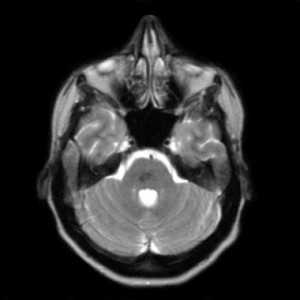

- Т1 и Т2

- извитые сосуды - в виде выпадения сигнала

- осложнения в виде кровоизлияний и отеков